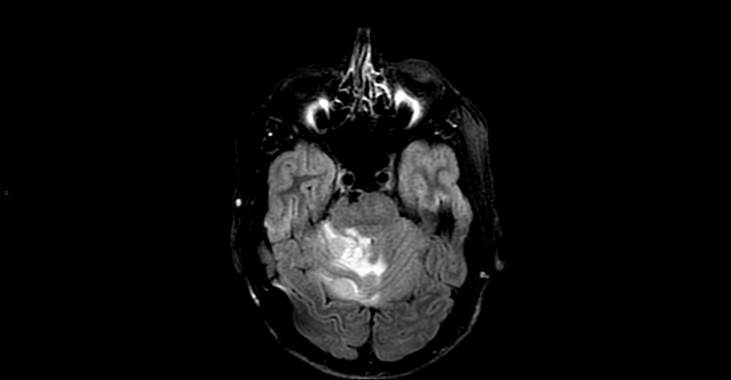

Hémangioblastome dans le cadre d’une maladie de Von Hippel Lindau